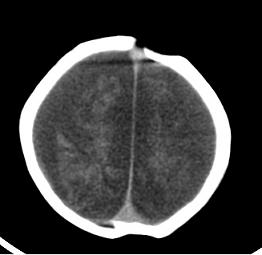

男,4个月大,2个月前无诱因下四肢抽搐、伴呕吐,近2天来抽搐频发,伴发热。查体:双眼疑视,神萎、纳差;颈抵抗,四肢张力高。

病史太长了,原因不好定,不过如果2个月前小儿正常的话可考虑积水型无脑畸形,积水型无脑畸形小儿刚生下来表现可正常,存活一两个月后出现症状.

另不除外缺血缺氧性脑病,感染等改变

2个月前缺血缺氧性脑病留下的后遗症。

脑出血后,软化灶形成了。脑发育不良

支持缺血缺氧性脑病留下的后遗改变(脑软化灶+脑发育不全+双侧慢性硬膜下积液+小头畸形)。

要注意化脓性脑膜、脑炎,硬膜下积脓,脑积水的可能,建议腰穿助诊。